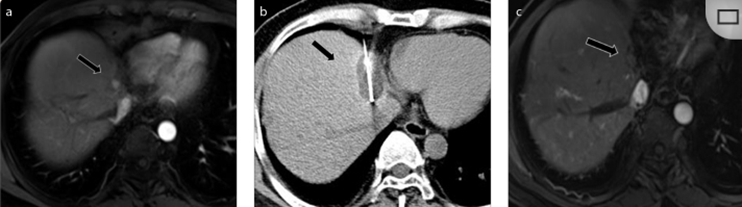

(a)軸向CT顯示病變位置毗鄰心臟和上腔靜脈(黑色箭頭)。1個月后的軸向(e)和冠狀位(f)增強CT掃描顯示低密度區(qū)域,由于肉芽組織反應引起的邊緣增強。